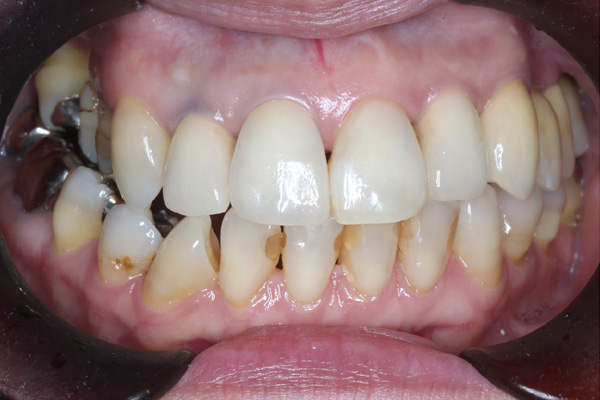

BEFORE

| 年代・性別 | 50代 男性 |

|---|---|

| 主訴 | 右上下の歯が痛い |

| 治療期間 | 約12ヶ月 |

| 費用 | 2,500,000円 |

| 治療内容 | インプラント、骨造成、結合組織移植、セラミック修復 |

| 治療に伴うリスク | インプラント周囲炎 セラミックの破折、脱離 |

*キャンセルポリシーをご一読のうえご予約ください